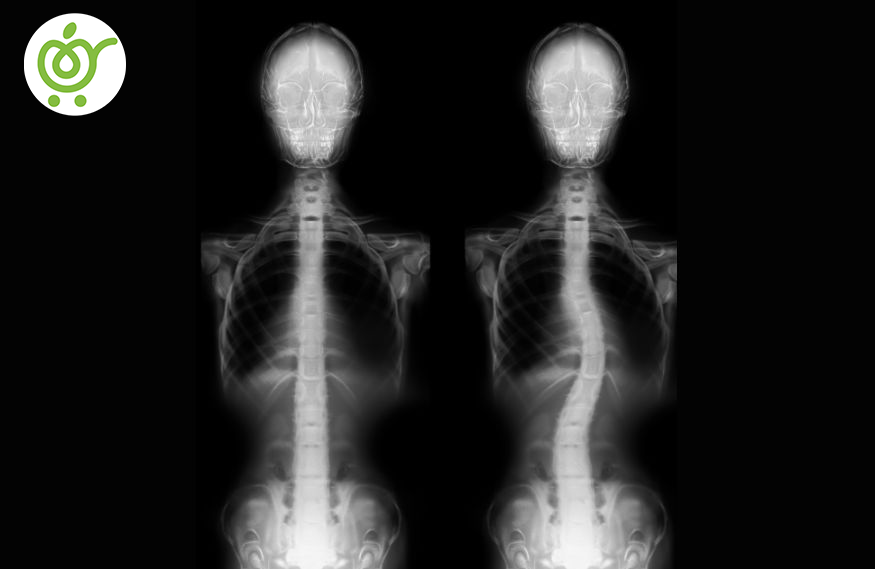

اسکولیوز یا کجی ستون فقرات

اسکولیوز یا همان کجی ستون فقرات، نوعی از انحراف ستون فقرات است که در سمت راست یا چپ ستون فقرات کمر دچار انحراف شود. این انحراف مختص گروه سنی خاصی نیست بلکه از سنین کودکی تا سنین بزرگسالی میتواند رخ دهد.

انحراف ستون فقرات اسکولیوز

زمانی که ستون فقرات به سمت راست یا چپ همانند تصویر، انحراف شود، این نوع انحراف ستون فقرات را اسکولیوز میگویند. اگر این عارضه، به آن مقدار نباشد که به وضوح دیده شود، میتوان گفت اسکولیوز از نوع خفیف میباشد که میتوانید با انجام تمرینات اصلاحی و همچنین برخی از راه و روشهای فیزیوتراپی، اصلاح شود. با وجود اینکه اسکولیوز هیچ درمانی ندارد، ولی با انجام این روش، از گسترش و حادتر شدن آن جلوگیری خواهید کرد.